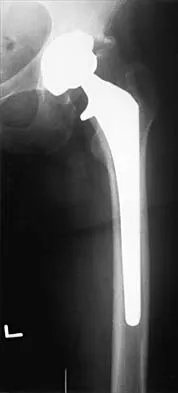

Figure 36a shows the current radiograph of a 65-year-old woman who slipped and fell. History reveals that prior to the fall she was actively functioning without pain. Figure 36b shows a radiograph obtained 1 year ago. Based on the fracture pattern, the failure is most likely related to

Detailed Explanation

The radiograph shows a fracture distal to the prosthesis in a stable, apparently well-fixed prosthetic stem. The well-fixed prosthesis-bone composite is stiff, creating a modulus mismatch between the proximal and distal femur. Therefore, the risk of fracture, particularly in osteoporotic bone, is increased at this level. Revision of the stem to a longer construct is unnecessary, and standard plate and screw fixation has been shown to yield union rates of greater than 90%. Nonsurgical treatment of fractures distal to the tip of the prosthesis results in high nonunion rates, reported to be from 25% to 42%. Johansson JE, McBroom R, Barrington TW, Hunter GA: Fracture of the ipsilateral femur in patients with total hip replacement. J Bone Joint Surg Am 1981;63:1435-1442. Bethea JS III, DeAndrade JR, Fleming LL, Lindenbaum SD, Welch RB: Proximal femoral fractures following total hip arthroplasty. Clin Orthop 1982;170:95-106.